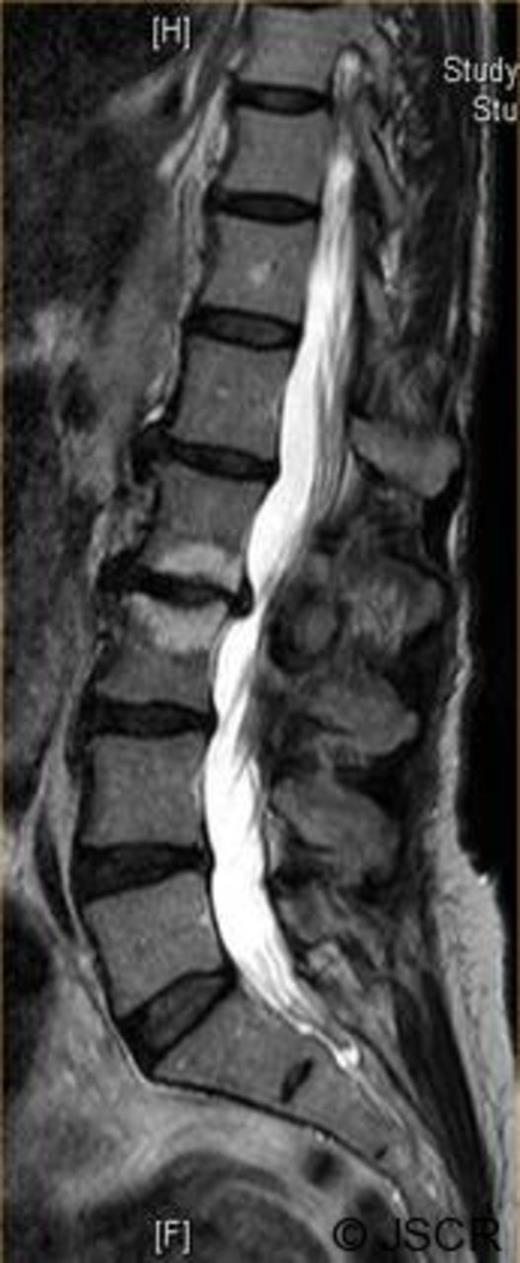

Magnetic Resonance Imaging scan (Fig. 1–4) showed L2/3 disc prolapse impinging on the right exit canal and causing L2 and L3 compression, thus she was listed for L2/3 lumbar discectomy and decompression. Examination of the right L2/L3 dermatomes revealed severe paresthesia and mild grade 4/5 weakness; reflexes were all normal. All other neurological examination was normal.

Preoperative axial T1 weighted image showing disc bulge at L2/3 to the right.